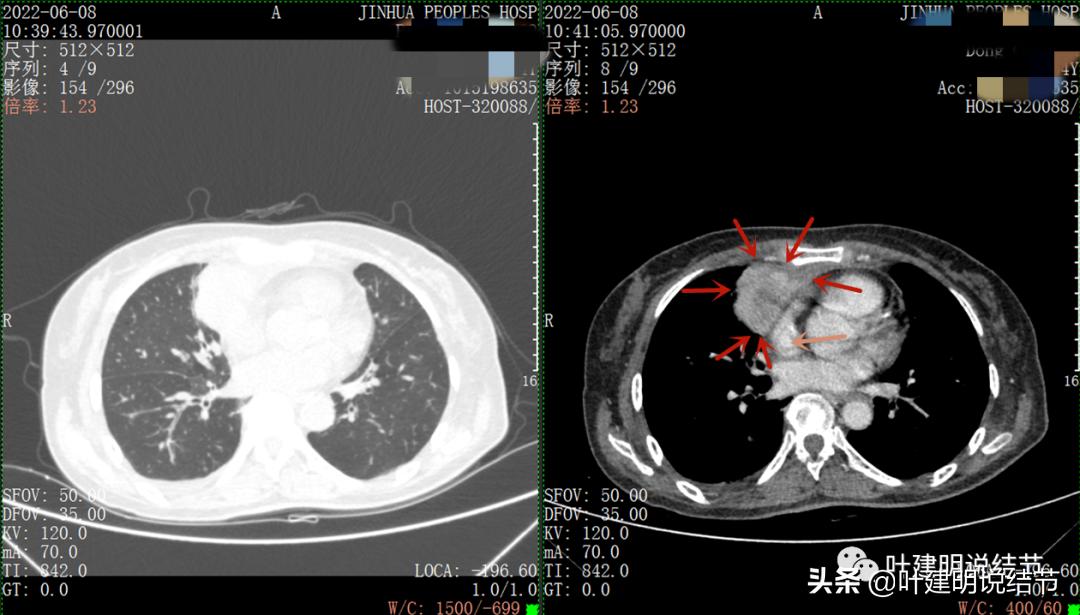

再来看看她的CT增强图像:

以下图片左侧是肺窗,右侧是纵隔窗。红色箭头示病灶,桔色箭头示无名静脉,黄色箭头示支气管,砖色箭头示上腔静脉,蓝色箭头示主动脉,紫色箭头示肺动脉。

病灶胸顶较高位置就出现了,在无名静脉水平

无名静脉略受压